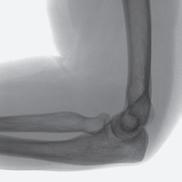

“One solution that we found is to use our Siemens MAGNETOM Free.Max 0.55T MRI Scanner,” says Dr. Seiberlich. As one of the few locations nationwide that owns and operates this “low field” machine, the MIITT team and UM Radiology have identified niche utilities, including the ability to conduct “in bore” biopsies--meaning the patient stays in the MRI scanner throughout the procedure. Now radiologists can clearly see the area that they want to biopsy, and accurately direct metallic needles without risk of damaging surrounding tissue. In addition to a wider bore, initially intended for larger patients or those with claustrophobia, the image quality of the scans is less affected by metal implants at low field strength. This is also advantageous when scanning patients with prior joint replacement surgery. “We can also capture MRI scans of parts of the body that are in motion, such as the heartbeat or blood flow,” she says. “Instead of a one second scan to make an image of a stationary body part, we can create a usable image in 20 milliseconds. We continue to discover special use cases that make this machine an exciting tool for us to have in radiology.”